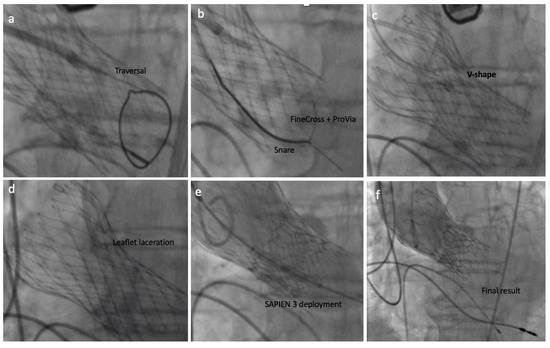

6.3. Procedure